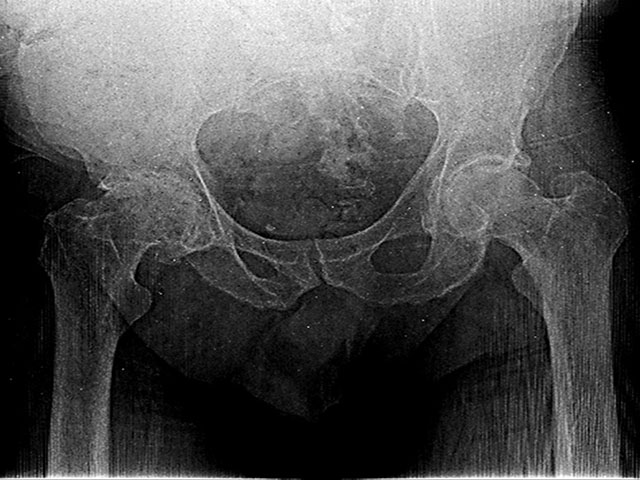

Hoy acudimos a tu buen corazón para apoyar a Henry Montilla, un hombre trabajador que actualmente enfrenta un duro desafío de salud. Henry ha sido diagnosticado con osteoartrosis de cadera derecha y osteonecrosis de la cabeza femoral.

Estas condiciones le provocan dolores intensos y constantes, restándole movilidad y, lamentablemente, impidiéndole caminar por sus propios medios. Su calidad de vida se ha visto gravemente afectada, pero existe una solución médica.

Para recuperar su autonomía y dejar atrás el dolor, Henry requiere una Artroplastia Total de Cadera. Este procedimiento permitirá reemplazar la articulación dañada por una prótesis, devolviéndole la posibilidad de ponerse en pie nuevamente.